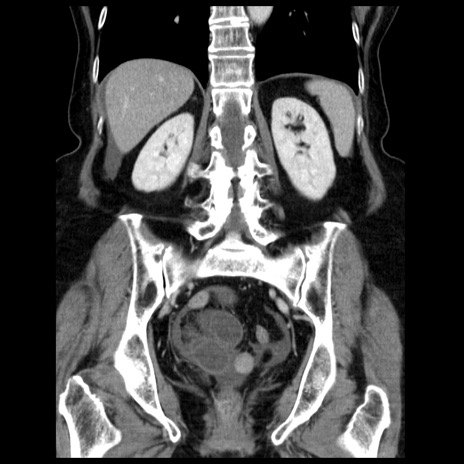

症例13(冠状断像)

【症例】70歳代女性

【主訴】腹痛、嘔吐

【現病歴】15時間程前(昨晩)より腹痛あり。今朝になっても症状の改善なく、嘔吐あり。腹痛も増悪あり、救急外来受診。

【既往歴】子宮癌全摘術後

【身体所見】意識清明、BP 121/72mmHg、P 74bpm、SpO2 100%(RA)、腹部:平坦・軟、腸雑音ほぼ聴取せず。下腹部・心窩部・臍左上に圧痛あり。反跳痛なし。

【データ】WBC 10600、CRP 0.15